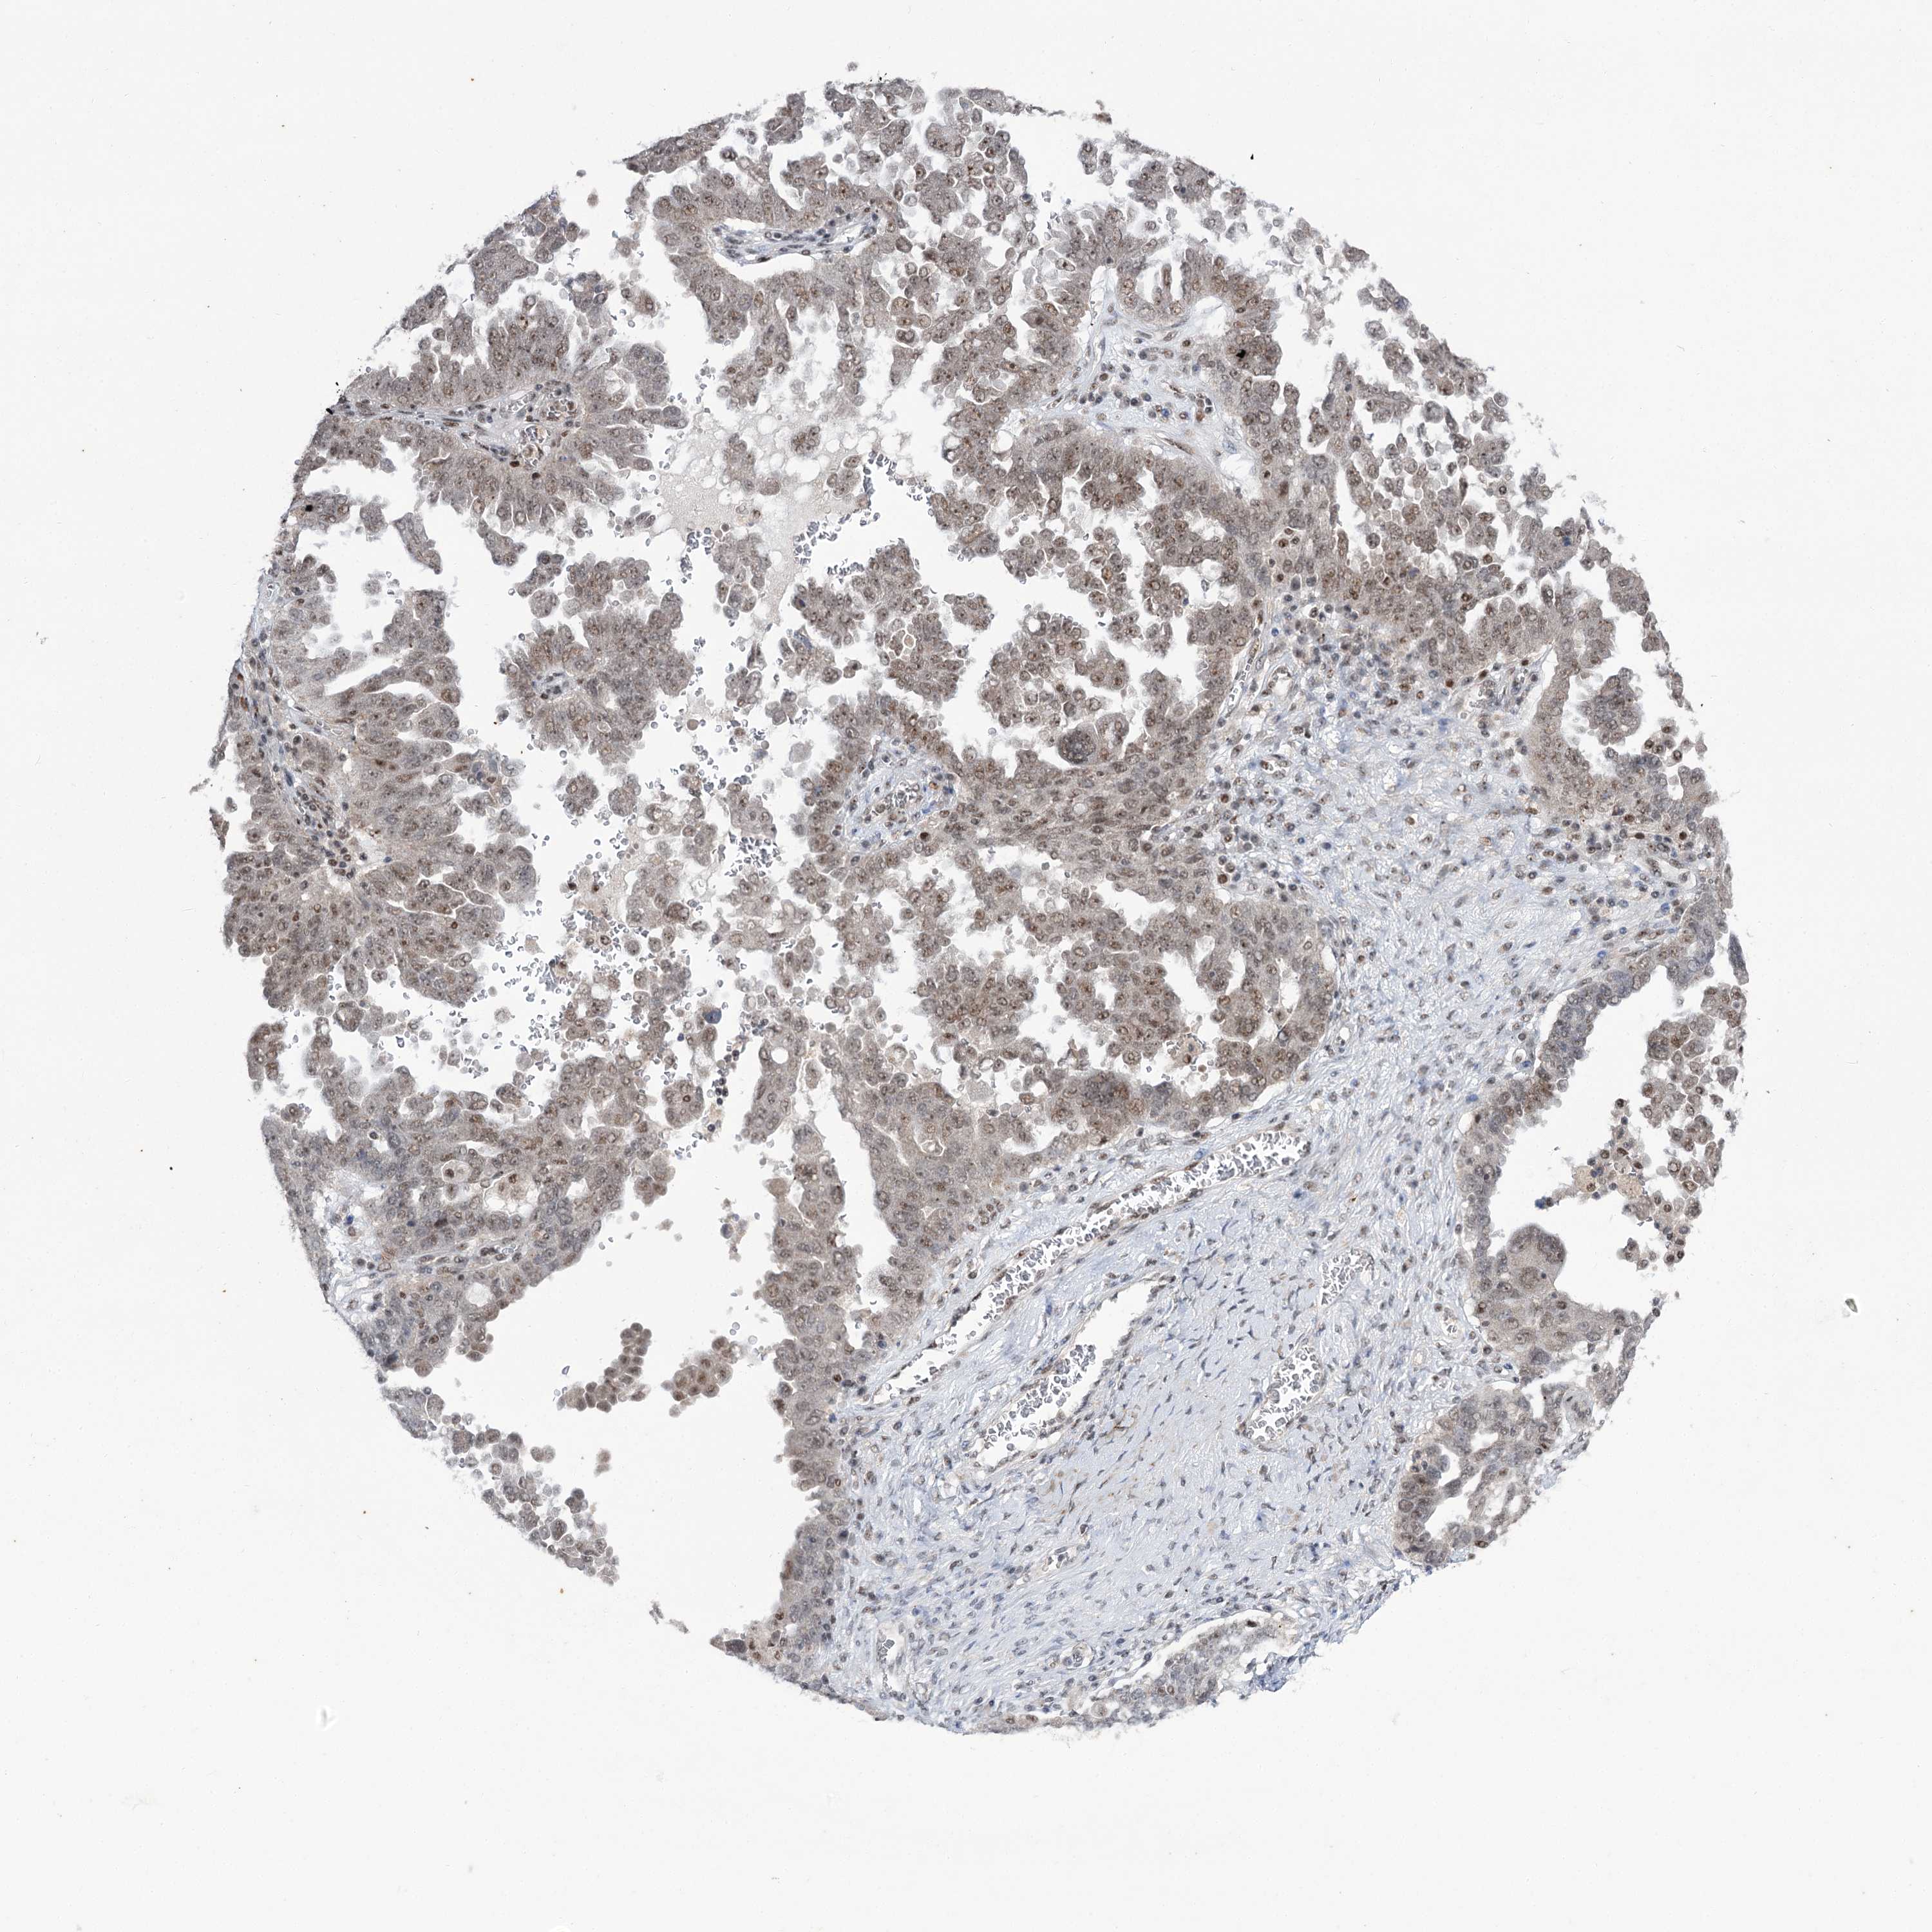

OVARIAN CANCER - Protein expressioni

A mouse-over function shows sample information and annotation data. Click on an image to view it in a full screen mode. Samples can be filtered based on level of antibody staining by selecting one or several of the following categories: high, medium, low and not detected. The assay and annotation is described here.

Note that samples used for immunohistochemistry by the Human Protein Atlas do not correspond to samples in the TCGA dataset.

Antibody stainingi

Antibody staining in the annotated cell types in the current human tissue is reported as not detected, low, medium, or high, based on conventional immunohistochemistry profiling in selected tissues. This score is based on the combination of the staining intensity and fraction of stained cells.

Each image is clickable and will lead to virtual microscopy that enables deeper exploration of all samples and also displays staining intensity scores, fraction scores and subcellular localization as well as patient and tissue information for each sample.

Antibody CAB037153

Staining

High

Medium

Low

Not detected

Intensity

Strong

Moderate

Weak

Negative

Quantity

>75%

75%-25%

<25%

None

Location

Nuclear

Cytoplasmic/membranous

Cytoplasmic/membranous,nuclear

Cystadenocarcinoma, serous, NOS

Carcinoma, endometroid

Cystadenocarcinoma, mucinous, NOS

Carcinoma, NOS